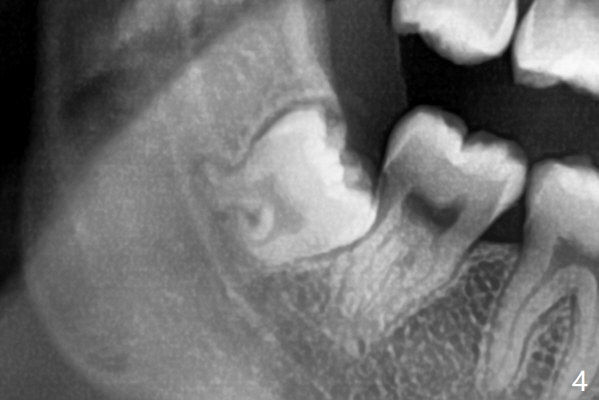

Since the third molars may overlap with the second ones, oblique incision (red line in Fig.4') will be mesial. Place Collagen and Osteogen plugs in the #32 and 17 sockets, respectively (Fig.4': C, O). As the roots are short and bone formation distal to the 2nd molars is critical, the plugs will be placed horizontally and coronally (Fig.4' white outline). No dovetail is needed.